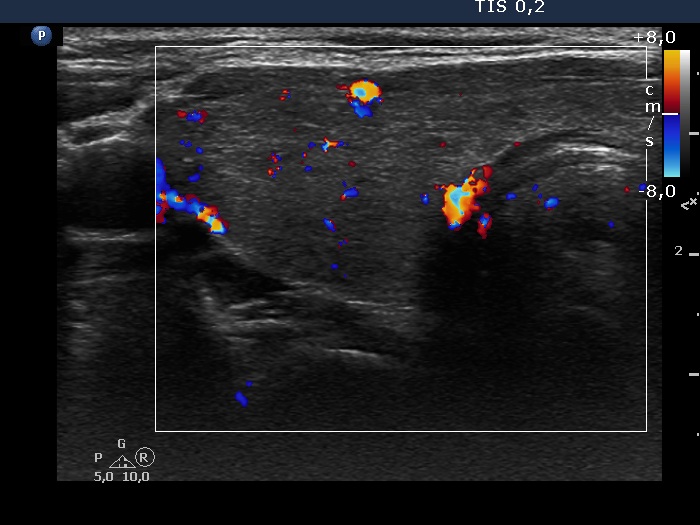

Consecutive patients with the final diagnosis of Hashimoto's thyroiditis - case 52 (1172) (ultrasonographic picture 4)

Right lobe, transverse view, color Doppler mode. The vascularization is not specific.